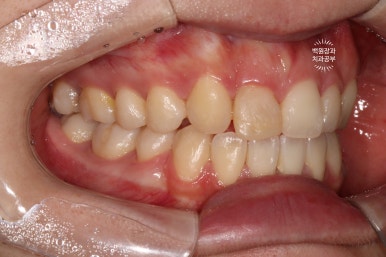

왼쪽: 우측 측면사진, 오른쪽: 좌측 측면사진

고개를 돌려 촬영한 사진을 보시면, 더욱 확실히 확인이 가능하실거에요.

우측 측면사진에 앞니가 하나 부족합니다. 정확히 얘기하면 대문니 - 중절치가 없죠.

교합면에서 보면, 앞니가 다섯개라는 것이 더 명확해집니다!!!